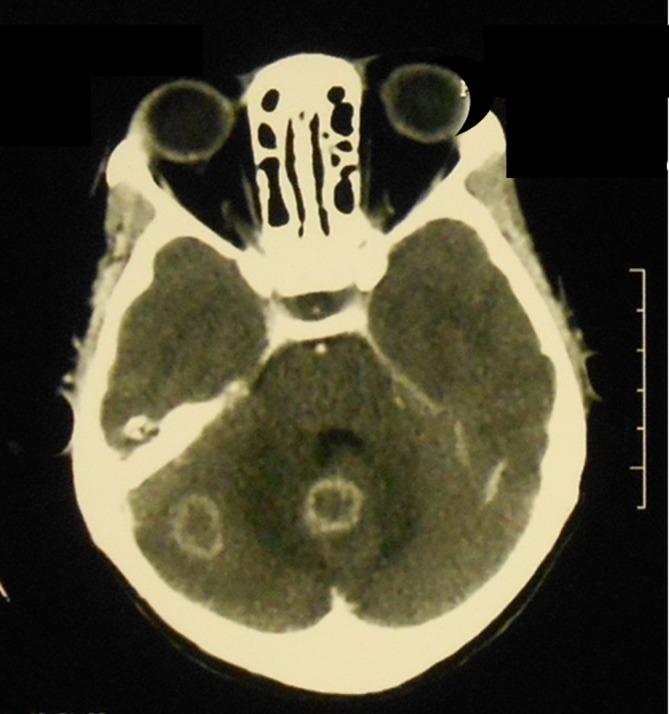

In recent years, most of the focus on improving the quality of paediatric care in low-income countries has been on improving primary care using the Integrated Management of Childhood Illness, and improving triage and emergency treatment in hospitals aimed at reducing deaths in the first 24 hours. There has been little attention paid to improving the quality of care for children with chronic or complex diseases. Children with complicated forms of tuberculosis (TB), including central nervous system and chronic pulmonary TB, provide examples of acute and chronic multisystem paediatric illnesses that commonly present to district-level and second-level referral hospitals in low-income countries. The care of these children requires a holistic clinical and continuous quality improvement approach. This includes timely decisions on the commencement of treatment often when diagnoses are not certain, identification and management of acute respiratory, neurological and nutritional complications, identification and treatment of comorbidities, supportive care, systematic monitoring of treatment and progress, rehabilitation, psychological support, ensuring adherence, and safe transition to community care. New diagnostics and imaging can assist this, but meticulous attention to clinical detail at the bedside and having a clear plan for all aspects of care that is communicated well to staff and families are essential for good outcomes. The care is multidimensional: biomedical, rehabilitative, social and economic, and multidisciplinary: medical, nursing and allied health. In the era of the Sustainable Development Goals, approaches to these dimensions of healthcare are needed within the reach of the poorest people who access district hospitals in low-income countries.

近年来,低收入国家提高儿科护理质量的工作重点大多放在通过儿童疾病综合管理改善初级护理,以及改善医院的分诊和急诊治疗以降低首24小时内的死亡率。对于改善慢性或复杂疾病患儿的护理质量,关注甚少。患有复杂形式结核病(包括中枢神经系统结核病和慢性肺结核)的儿童,是低收入国家地区级和二级转诊医院常见的急性和慢性多系统儿科疾病的例子。对这些儿童的护理需要全面的临床和持续质量改进方法。这包括在诊断往往不确定时及时决定开始治疗,识别和管理急性呼吸、神经和营养并发症,识别和治疗合并症,提供支持性护理,系统监测治疗和进展情况,进行康复治疗、心理支持,确保依从性,以及安全过渡到社区护理。新的诊断方法和成像技术可以提供帮助,但在床边细致关注临床细节,并为护理的各个方面制定清晰的计划并与工作人员和家庭进行良好沟通,对于取得良好结果至关重要。护理是多维度的:生物医学、康复、社会和经济方面;也是多学科的:医疗、护理和相关健康领域。在可持续发展目标的时代,低收入国家中前往地区医院就诊的最贫困人口需要能够获得针对医疗保健这些维度的方法。